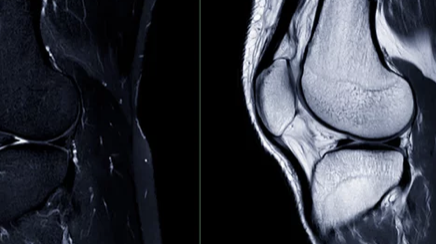

- X-ray: 뼈 손상 여부를 확인

- MRI: 연골 상태를 정확하게 진단

- CT: 뼈와 연골 상태를 자세하게 확인